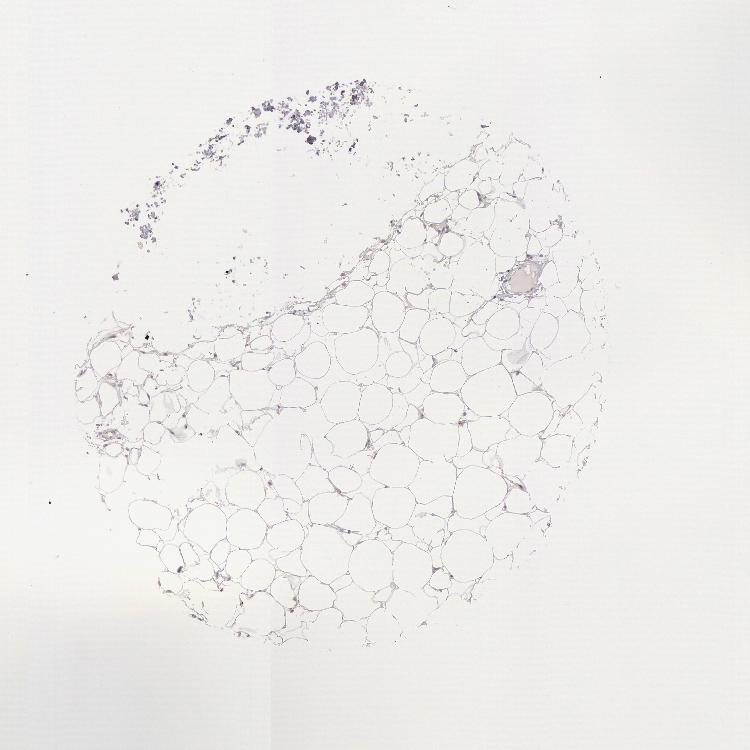

SOFT TISSUE 1 - Antibody stainingi

Antibody staining in the annotated cell types in the current human tissue is reported as not detected, low, medium, or high, based on conventional immunohistochemistry profiling in selected tissues. This score is based on the combination of the staining intensity and fraction of stained cells.

Each image is clickable and will lead to virtual microscopy that enables deeper exploration of all samples and also displays staining intensity scores, fraction scores and subcellular localization as well as patient and tissue information for each sample.

Antibody HPA001272

Chondrocytes Not detected

Fibroblasts Not detected

Peripheral nerve Not detected